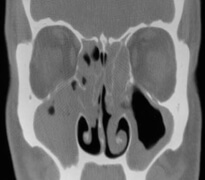

단순 부비동 촬영 검사와 부비동 전산화 단층촬영(CT 촬영)을 시행합니다.

전산화 단층촬영은 부비동과 인접한 구조물을 평가하는 데 가장 유용한 검사입니다.

이를 통해 상악동의 전벽, 후벽, 측벽의 상태를 동시에 확인하고, 종양의 침윤 정도를 쉽게 관찰할 수 있습니다.

아울러 사골동, 접형동, 안와 내 시신경, 시신경관 등의 이상 유무를 보여 줍니다.